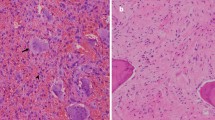

Several cases of sarcomatous transformation in recurrent GCTB have been described, for example in the tibia with transformation into a high-grade pleomorphic sarcoma after 13 months on denosumab treatment [52] and transformation into a high-grade osteosarcoma in the ischium after 6 months on treatment [53]. Transformation into different types of sarcoma has been described, including undifferentiated pleomorphic sarcoma, fibrosarcoma and osteosarcoma [12, 54].

The key clinical findings that point towards sarcomatous transformation are worsening or new onset of pain and growth of the lesion during treatment. Absence of expected radiological findings during denosumab treatment, particularly lack of peripheral or central matrix osteosclerosis formation and decreased 18F-FDG-PET avidity, should alert clinicians to the possibility of misdiagnosis or sarcomatous change. Secondary malignant GCTB may present as an aggressive osteolytic tumour with cortical destruction and a soft tissue component [55]. Unfortunately, imaging findings for malignant transformation are not specific, given that both benign and malignant GCTB can show aggressive features [50, 51, 54].

Misdiagnosis of the primary or of the recurrent tumour is another pitfall [16]. Histopathology of denosumab-treated GCTB tumours may resemble that of low-grade central osteosarcoma due to new bone formation in a fibrous background [56]. Benign multinucleated giant cells may be present in up to 36% of low-grade central osteosarcomas, making the distinction more challenging [57]. Genetic analyses such as the H3F3A mutation (present in giant cell-rich sarcomas) may be needed to distinguish the two tumours. These findings underline the need of a specialized tertiary sarcoma referral centre so that cases can be discussed and reviewed with expert bone tumour pathologists. It is essential that the correct clinical context of biopsy specimens is provided to the pathologist, specifically details regarding radiotherapy, denosumab therapy and clinical and radiological response to treatment.